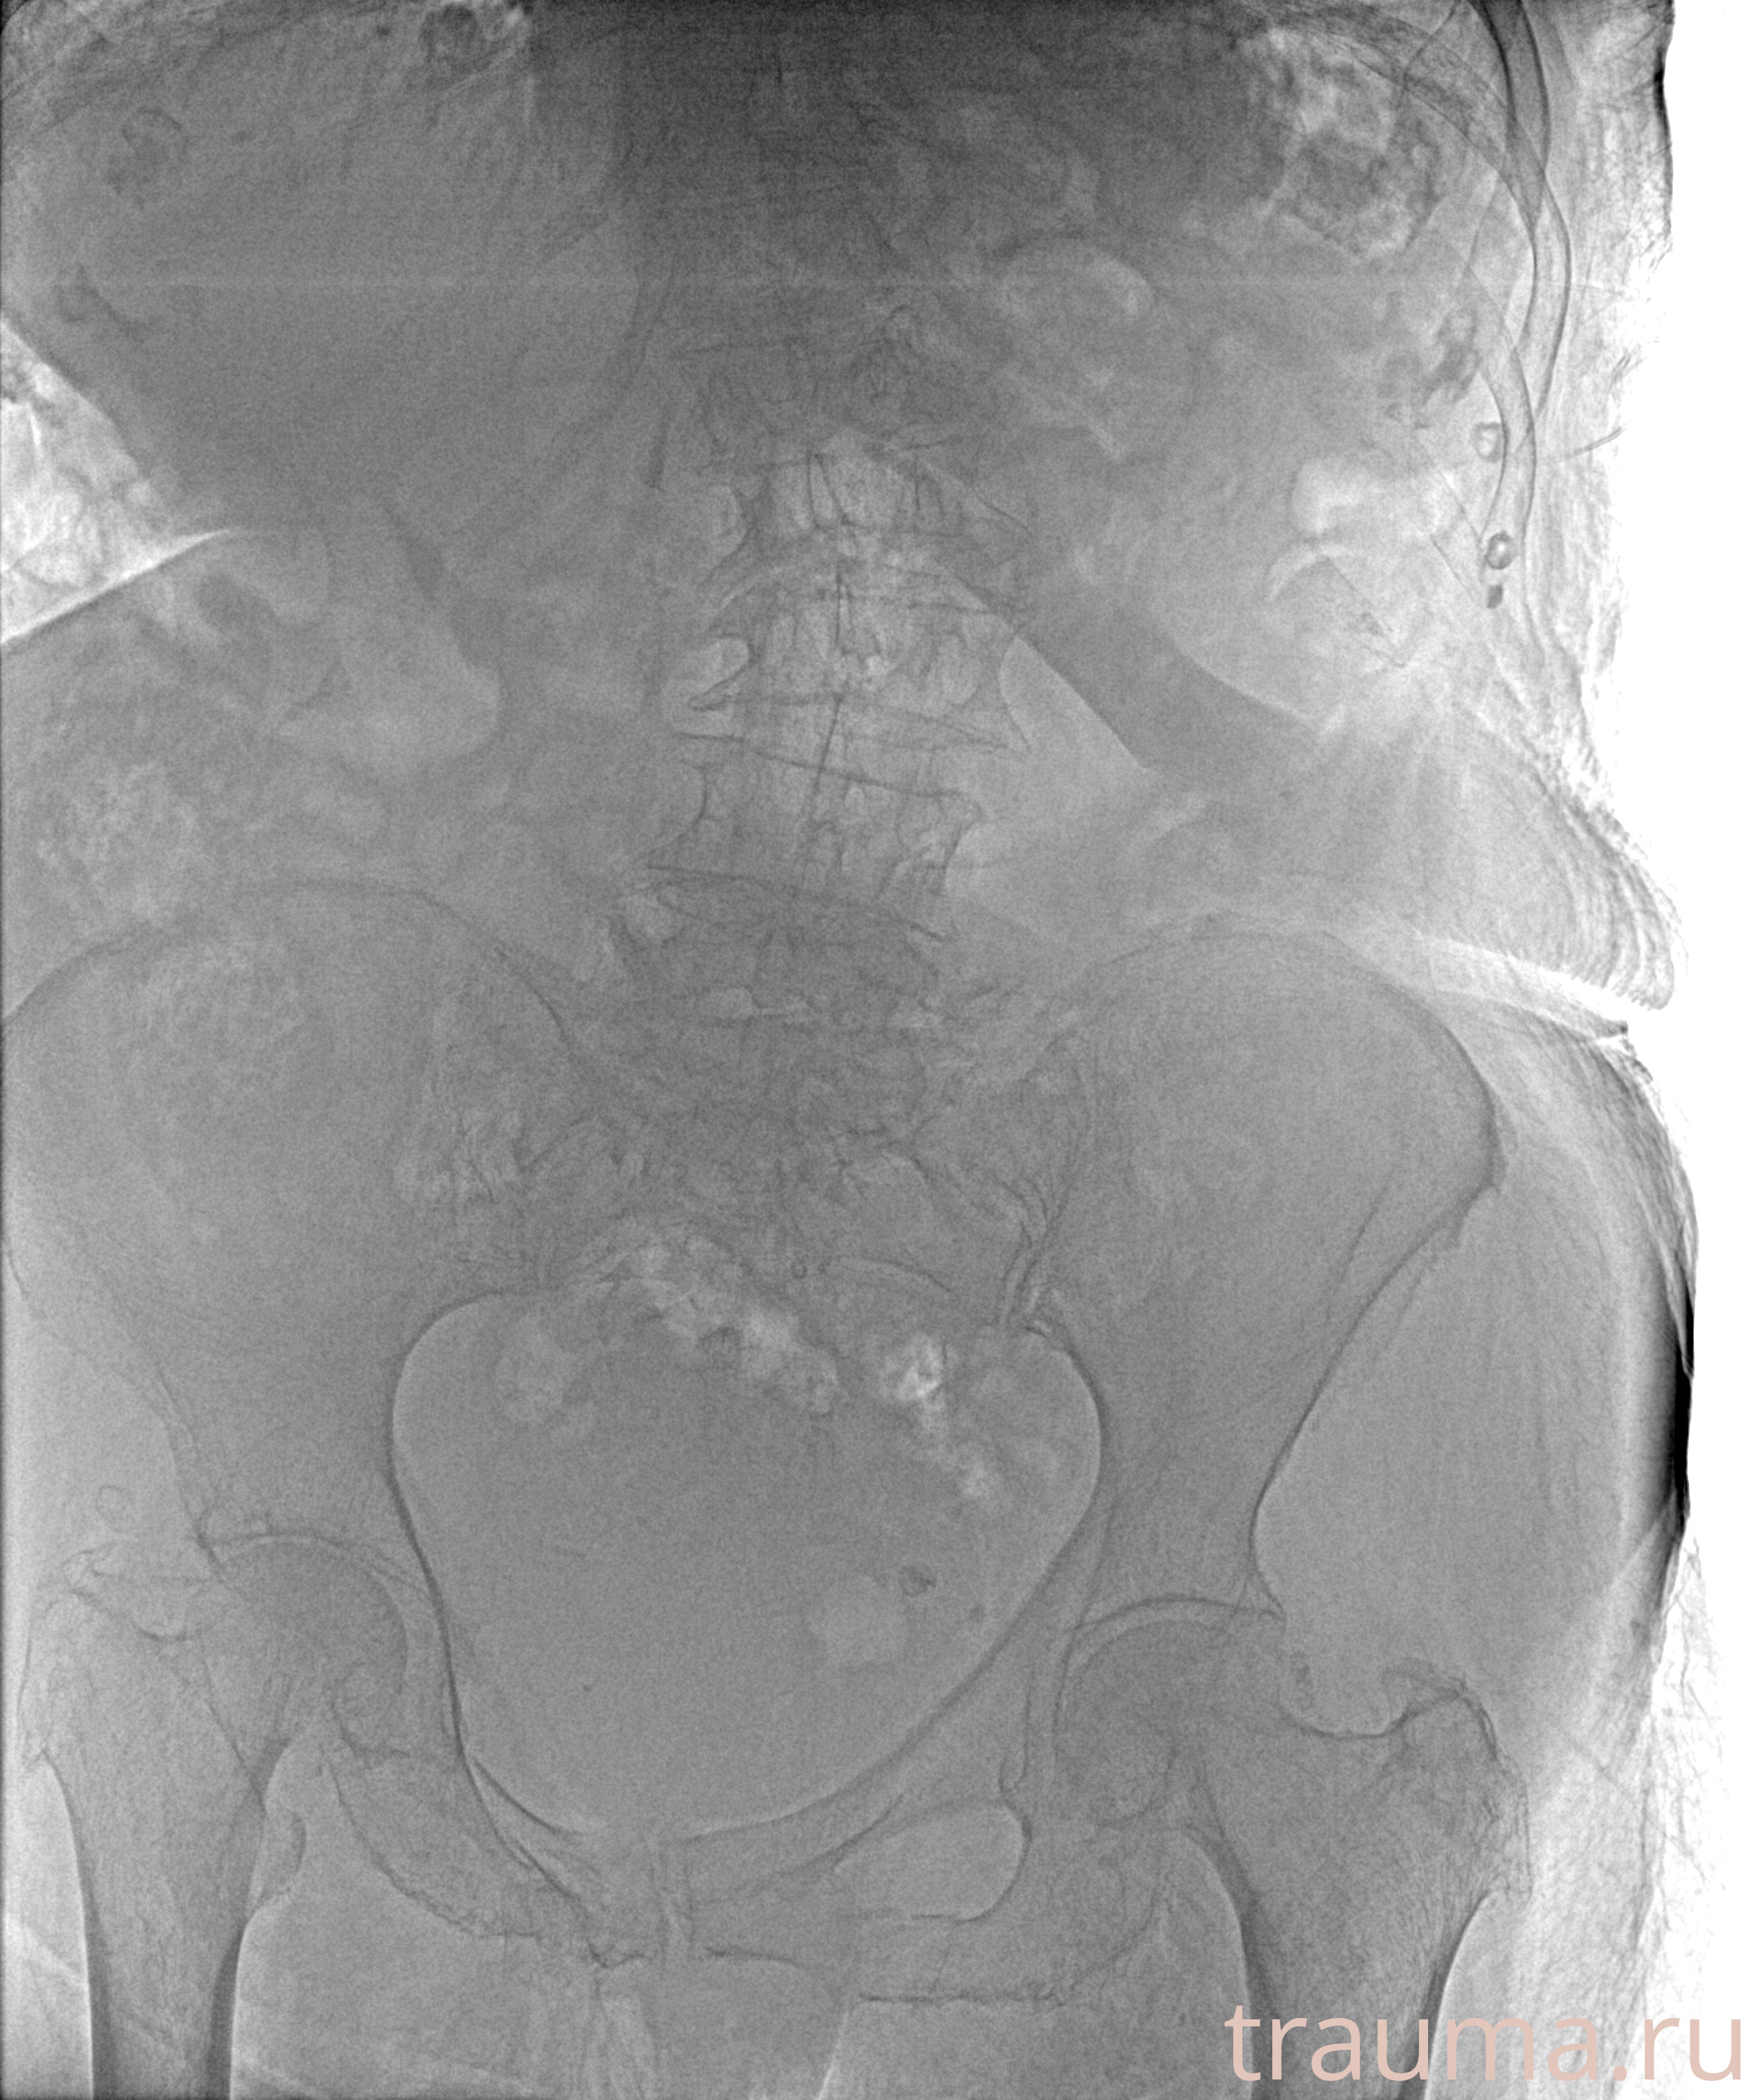

Рентгенограммы

Рентген на дому: по вашему адресу приезжает врач-рентгенолог, травматолог-ортопед с мобильным рентгеновским аппаратом, проводит диагностику травмы или заболевания, делает необходимые рентгенограммы, дает рекомендации по дальнейшему лечению. Получить качественные снимки в домашних условиях возможно благодаря уникальной методике, разработанной МосРентген Центром для института  Склифосовского

при переломе шейки бедра и пневмонии от компании МосРентген Центр - партнера Института имени Склифосовского